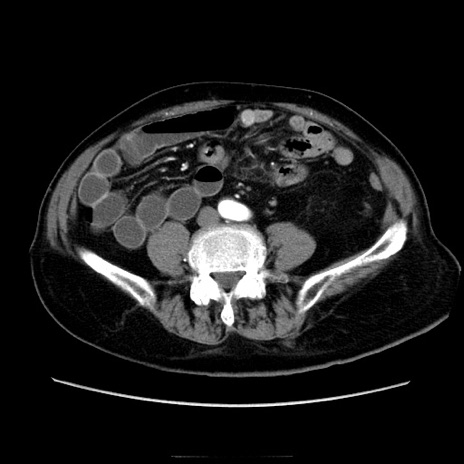

症例21(横断像)

【症例】70歳代男性

【主訴】腹痛

【現病歴】肝硬変・肝細胞癌にてかかりつけの方。約9時間前に食後より腹痛出現。症状が徐々に増悪し、嘔吐出現したため来院。

【既往歴】肝硬変、肝細胞癌(RFA、TACE後)

【身体所見】意識清明、表情苦悶様、BT 36℃、BP 129/78mmHg、P 88bpm、SpO2 97%(RA)、右上腹部から心窩部にかけて圧痛あり、反跳痛なし、筋性防御あり。

【データ】WBC 5800、CRP 0.16